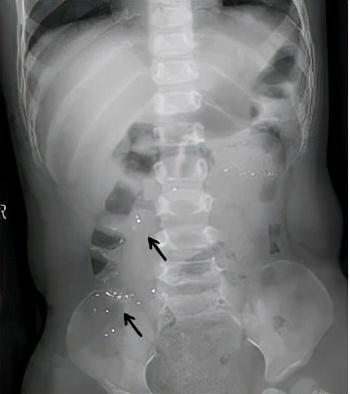

我们通过拍照可以清楚的看到肚子里的水银颗粒!

6、及时就医,必要时可以拍X线片观察下汞在胃肠道内的部位。